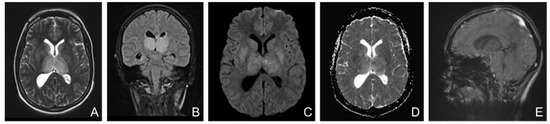

Figure 3. (AD): Unenhanced brain MRI (at 3 months): (A)—Fluid attenuated inversion recovery (FLAIR) coronal, (B)—Diffusion-weighted imaging (DWI) axial, (C)—T2* hemo axial, (D)—T1 sagittal: Chronic ischemic left parietal lesion with hemorrhagic transformation partially resolved. E-H: Unenhanced and enhanced brain MRI (at six years): (E)—FLAIR coronal, (F)—DWI axial, (G)—T2* hemo axial, (H)—T1 sagittal after i.v. contrast administration: Chronic ischemic left parietal lesion with slightly peripheral gliosis, without restricted diffusion and minimal hemosiderin peripheral deposits, without filling defect of the veins and venous sinuses.

Close monitoring was performed after discharge, clinically, biologically, and radiologically. Three months after the CVT, she had completely recovered all her motor functions with the use of neurorehabilitation therapy. However, she developed symptoms of depression, for which she started receiving antidepressant medication. The brain MRI (Figure 3) showed the lesion as being chronic with the hemorrhage partially resolved at three months, with an aspect of organizing hematoma.

Three years later, she underwent another brain MRI (Figure 3) that showed a chronic ischemic left parietal lesion with partial peripheral gliosis and peripheral hemosiderin deposits.

A follow-up brain MRI at six years showed the chronic lesion with no filling defect of cerebral veins and sinuses.